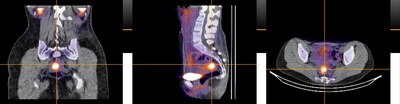

This was an exploratory, open-label, single-centre, phase 2 study evaluating preoperative imaging in 20 individuals with suspected or confirmed pelvic or thoracic endometriosis using a SPECT-CT, with intravenous 99mTc-maraciclatide. The primary outcome was alignment of radiological and surgical findings in those patients completing both imaging and surgery. The surgical report on lesion type and location was compared to images for alignment. The study was funded by the NIHR Oxford Biomedical Research Centre and Serac Healthcare. Scans were performed at the Royal United Hospital, Bath.

Photo: https://mma.prnewswire.com/media/2970155/DETECT_Study.jpg